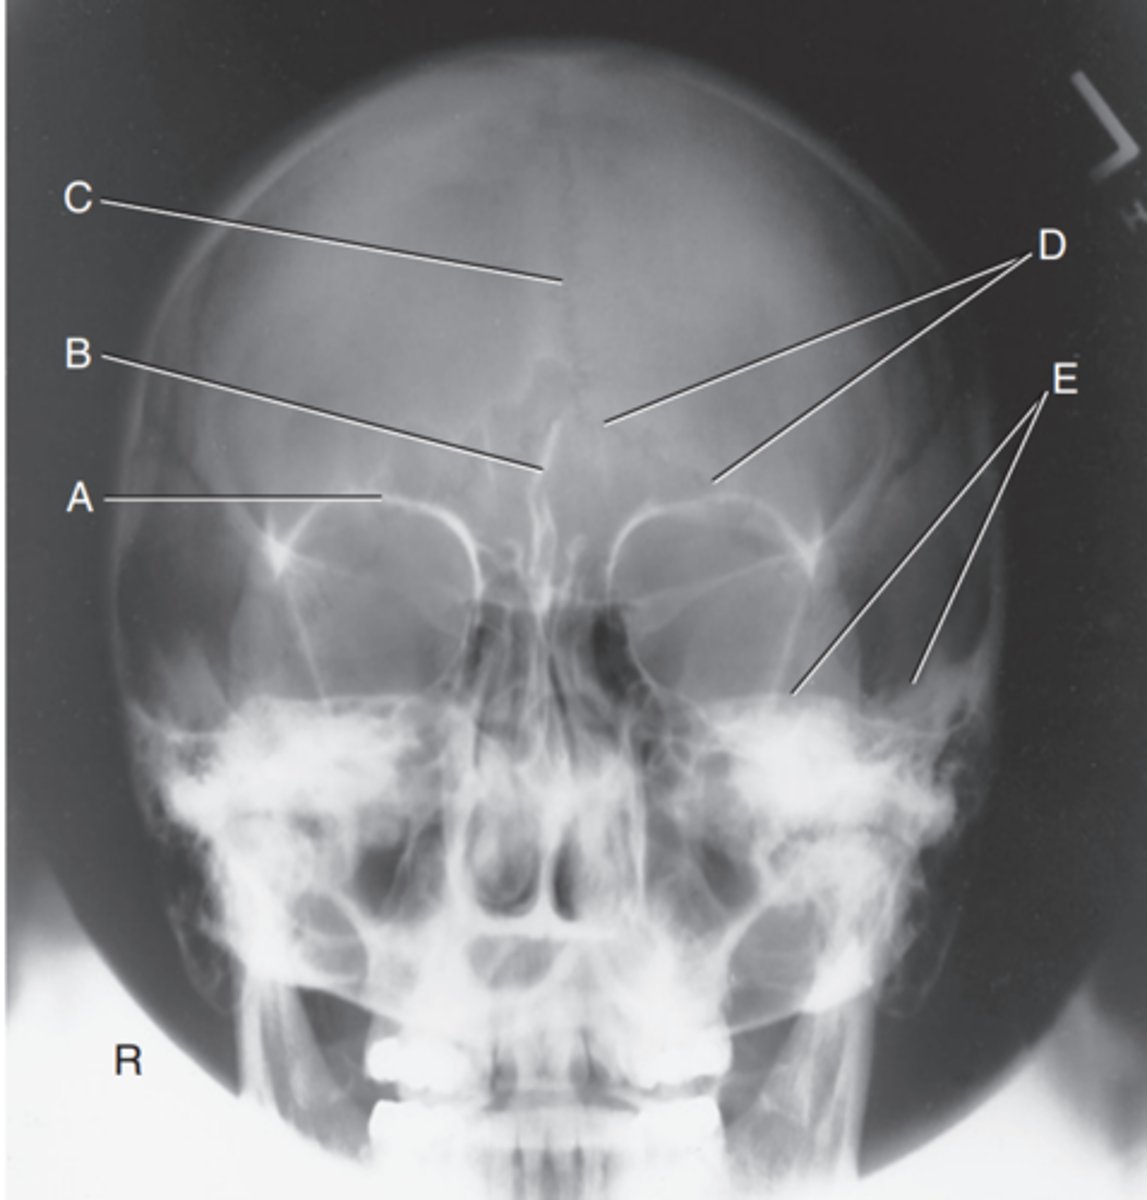

Supraorbital margin of right orbit

Label A

Crista galli of ethmoid

Label B

Sagittal suture

Label C

Lambdoidal suture

Label D

Petrous ridge

Label E